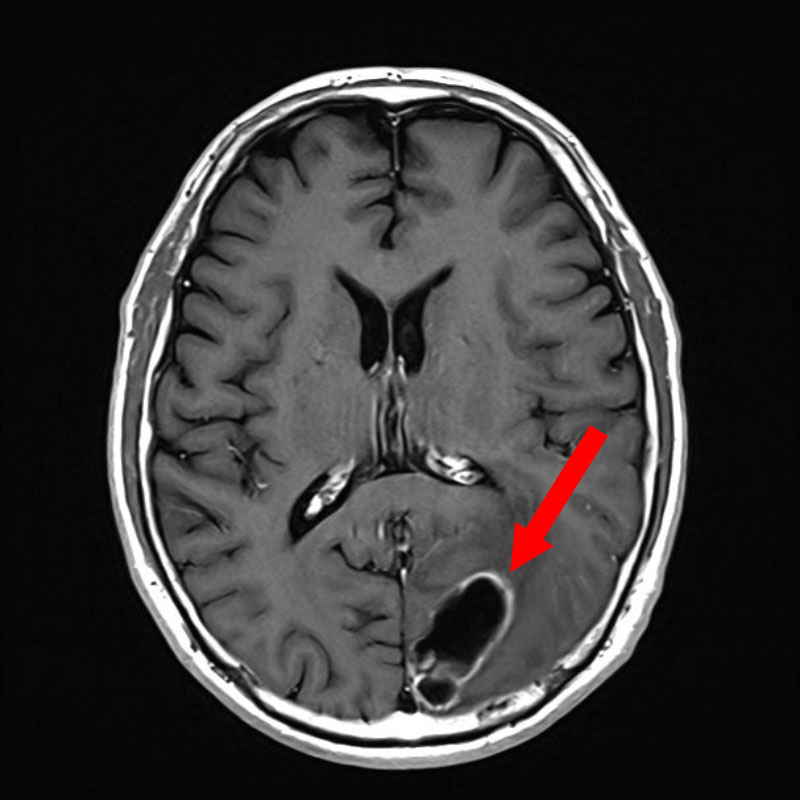

断層撮影

手術前1